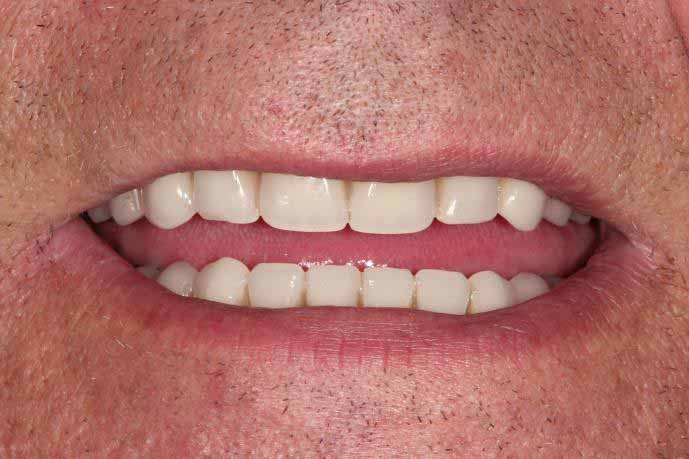

Same Day All on 4 Dental Implants Treatment

This patient had missing teeth and the those that remained were failing. After discussing with the patient, it was decided to remove the failing teeth and rehabilitate with same day all on 4 dental implants.

This treatment is usually carried out in 1 day (after a few preparatory appointments for moulds, x-rays, etc). The failing teeth were removed and implants place on the same day, with a temporary bridge (fixed teeth) attached also on the same day. Following a period of 3 to 6 months, moulds were taken and the definitive bridge placed